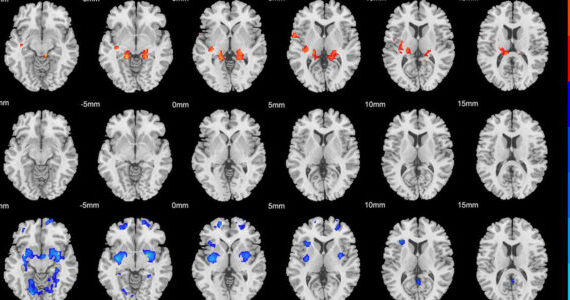

Brain scans reveal a bipolar-like link to childhood trauma in some depressed patients

By Shop Psychology